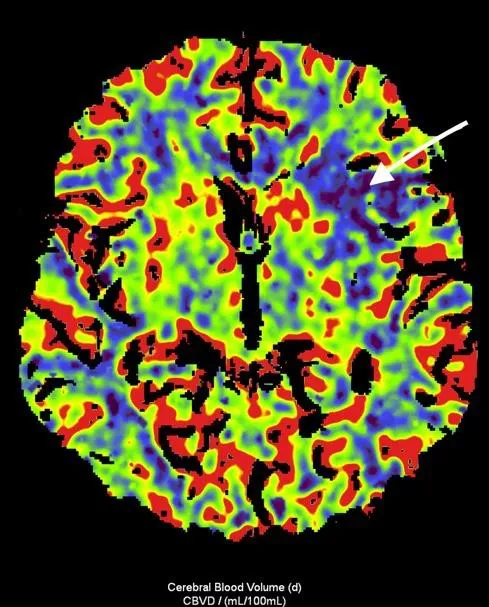

Рисунок 3. МСКТ-перфузійні зображення пацієнта Д.

Представлені карти МСКТ-перфузійних зображень демонструють зони дуже низької перфузії при CBV (a) та CBF (b), що відповідають ядру інфаркту (біла стрілка), та велику зону, що відповідаї пенумбрі (зелений овал) при TMax-map (c).

Відповідно до результатів нейровізуалізації та візуалізації церебральних артерій у пацієнта Д. був діагностований ішемічний інсульт, що обумовлений оклюзією великої мозкової артерії (лівої внутрішньої сонної артерії [ВСА] та лівої середньої мозкової артерії [СМА]). Згідно з результатами автоматичного обчислення, на момент дослідження об’єм ядра інфаркту у пацієнта Д. склав 24,6 см3, а об’єм зони пенумбри – 47,9 см3. Отже, об’єм зони пенумбри становив 194,7% об’єму ядра (співвідношення пенумбри та інфаркта майже 2:1). Зважаючи на це, ситуація була обговорена з лікарем-нейрохірургом С. В. Конотопчиком і о 14:45 пацієнт бригадою НМД «Оберіг» був доправлений у ДУ «НПЦ Ендоваскулярної нейрорентгенохірургії НАМН України» та спрямований одразу до операційної.